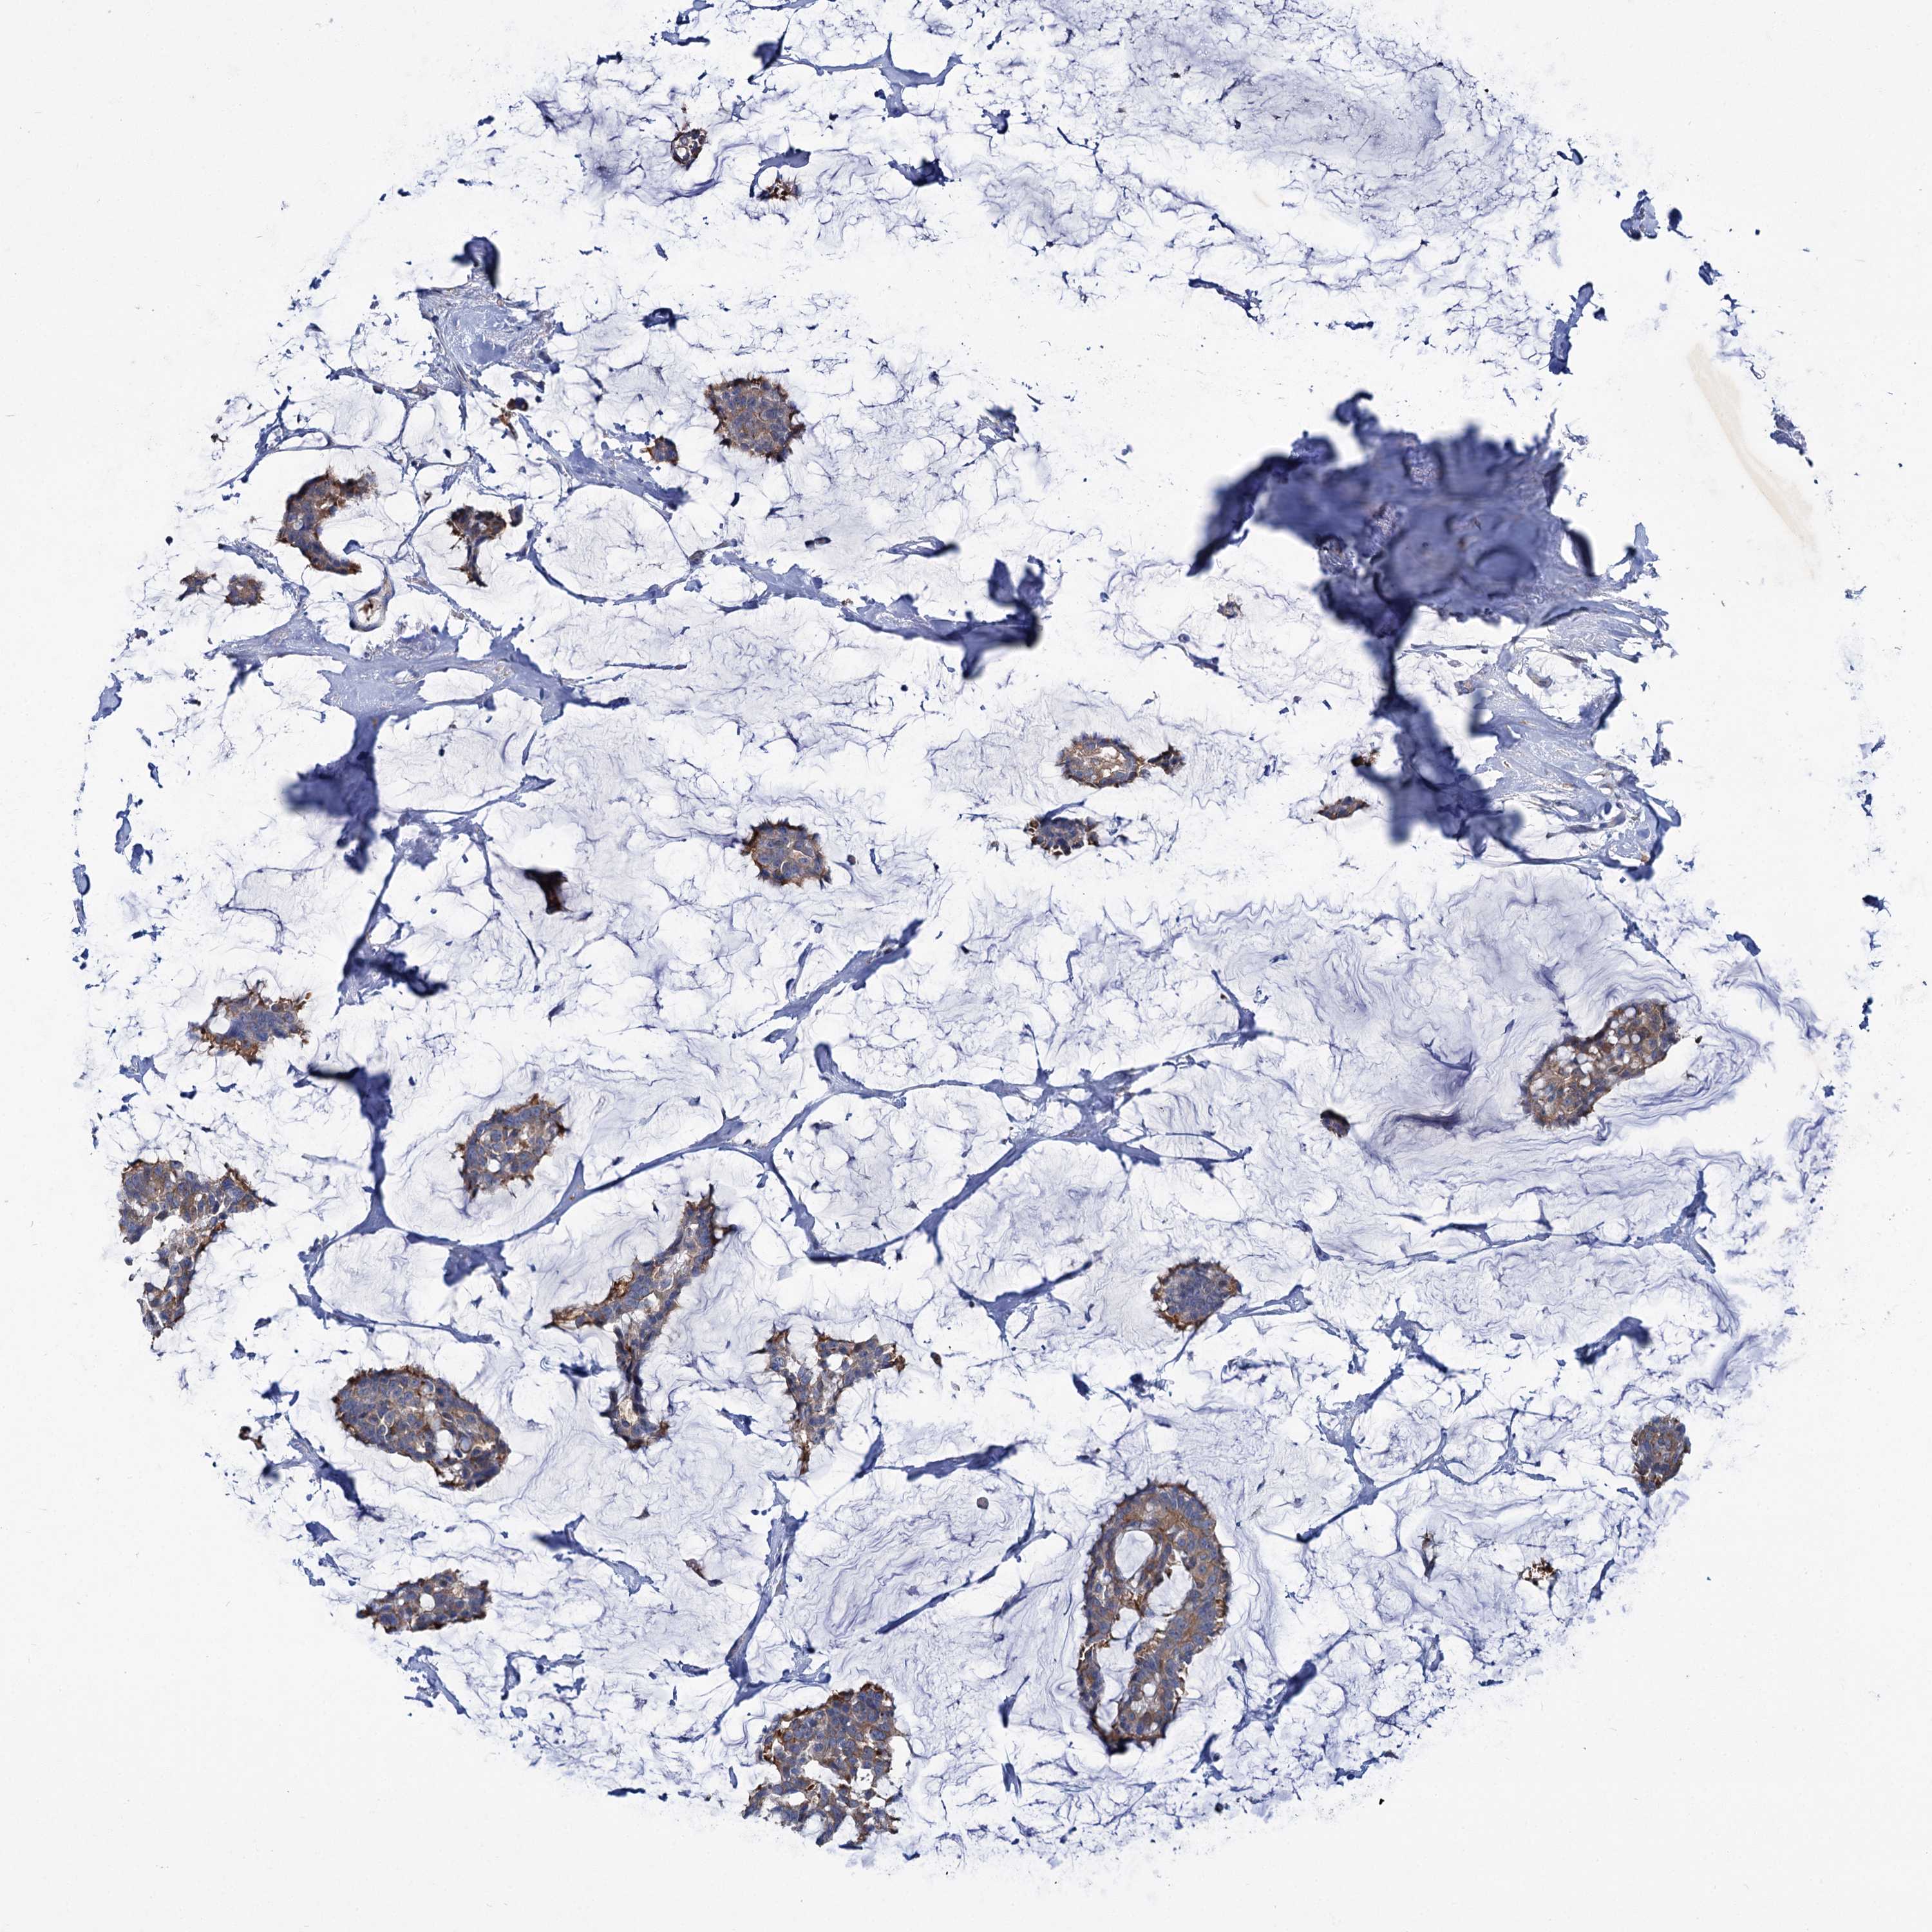

CANCER BREAST CANCER Show tissue menu

BRCA TCGA BRCA VALIDATION PROTEIN EXPRESSION

ANTIBODIES

AND

VALIDATION